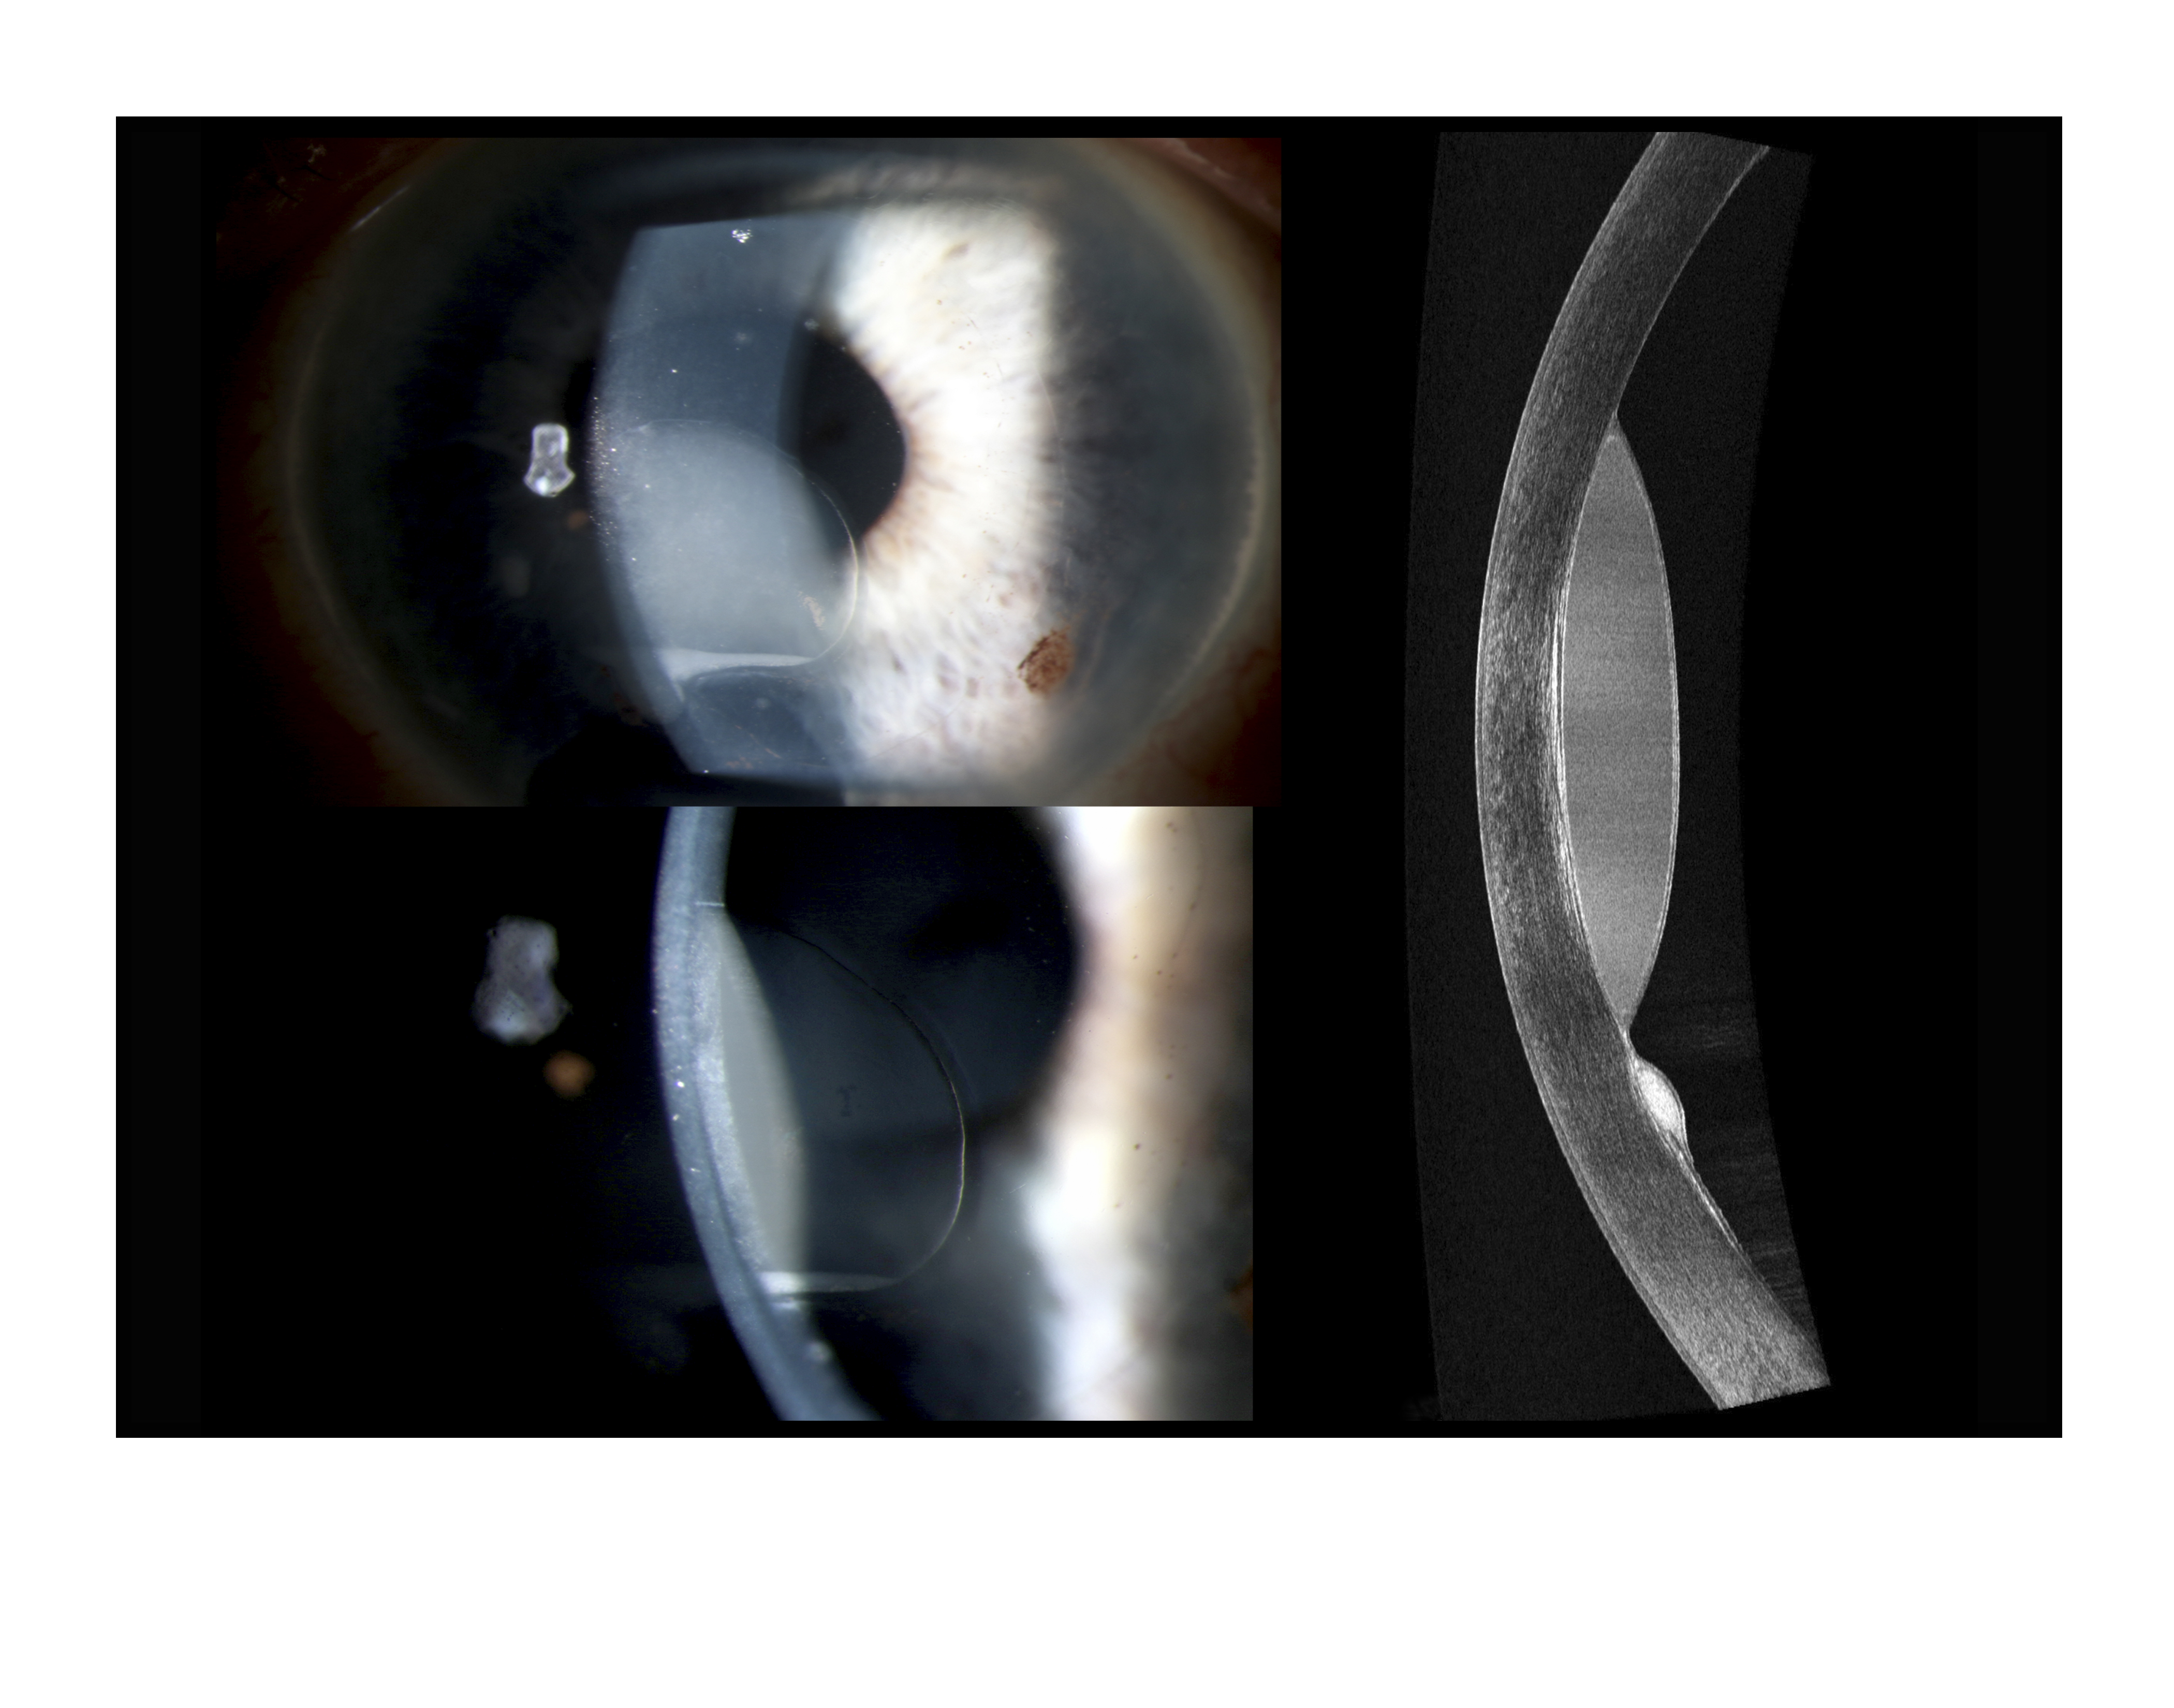

Corneal Epithelial Ingrowth

Presented by Mark Harrod, CRA, OCT-C

This photograph received Second Place in the category "Cross Categories" and was displayed in the 2024 OPS Exhibit.